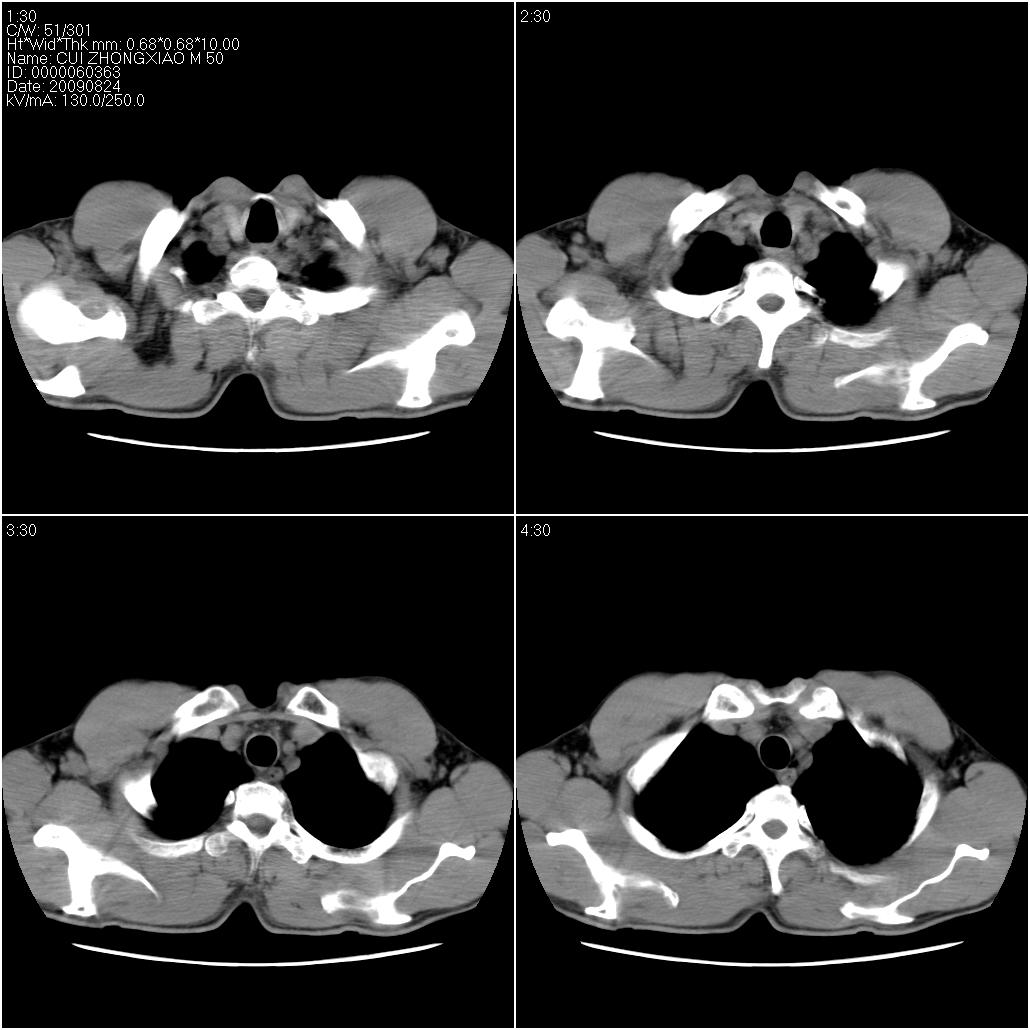

标题: CT21851:男性,50岁。间断性咳嗽半年。 [打印本页]

标题: CT21851:男性,50岁。间断性咳嗽半年。

考虑以感染性病变,以结核可能性大,建议治疗后复查。